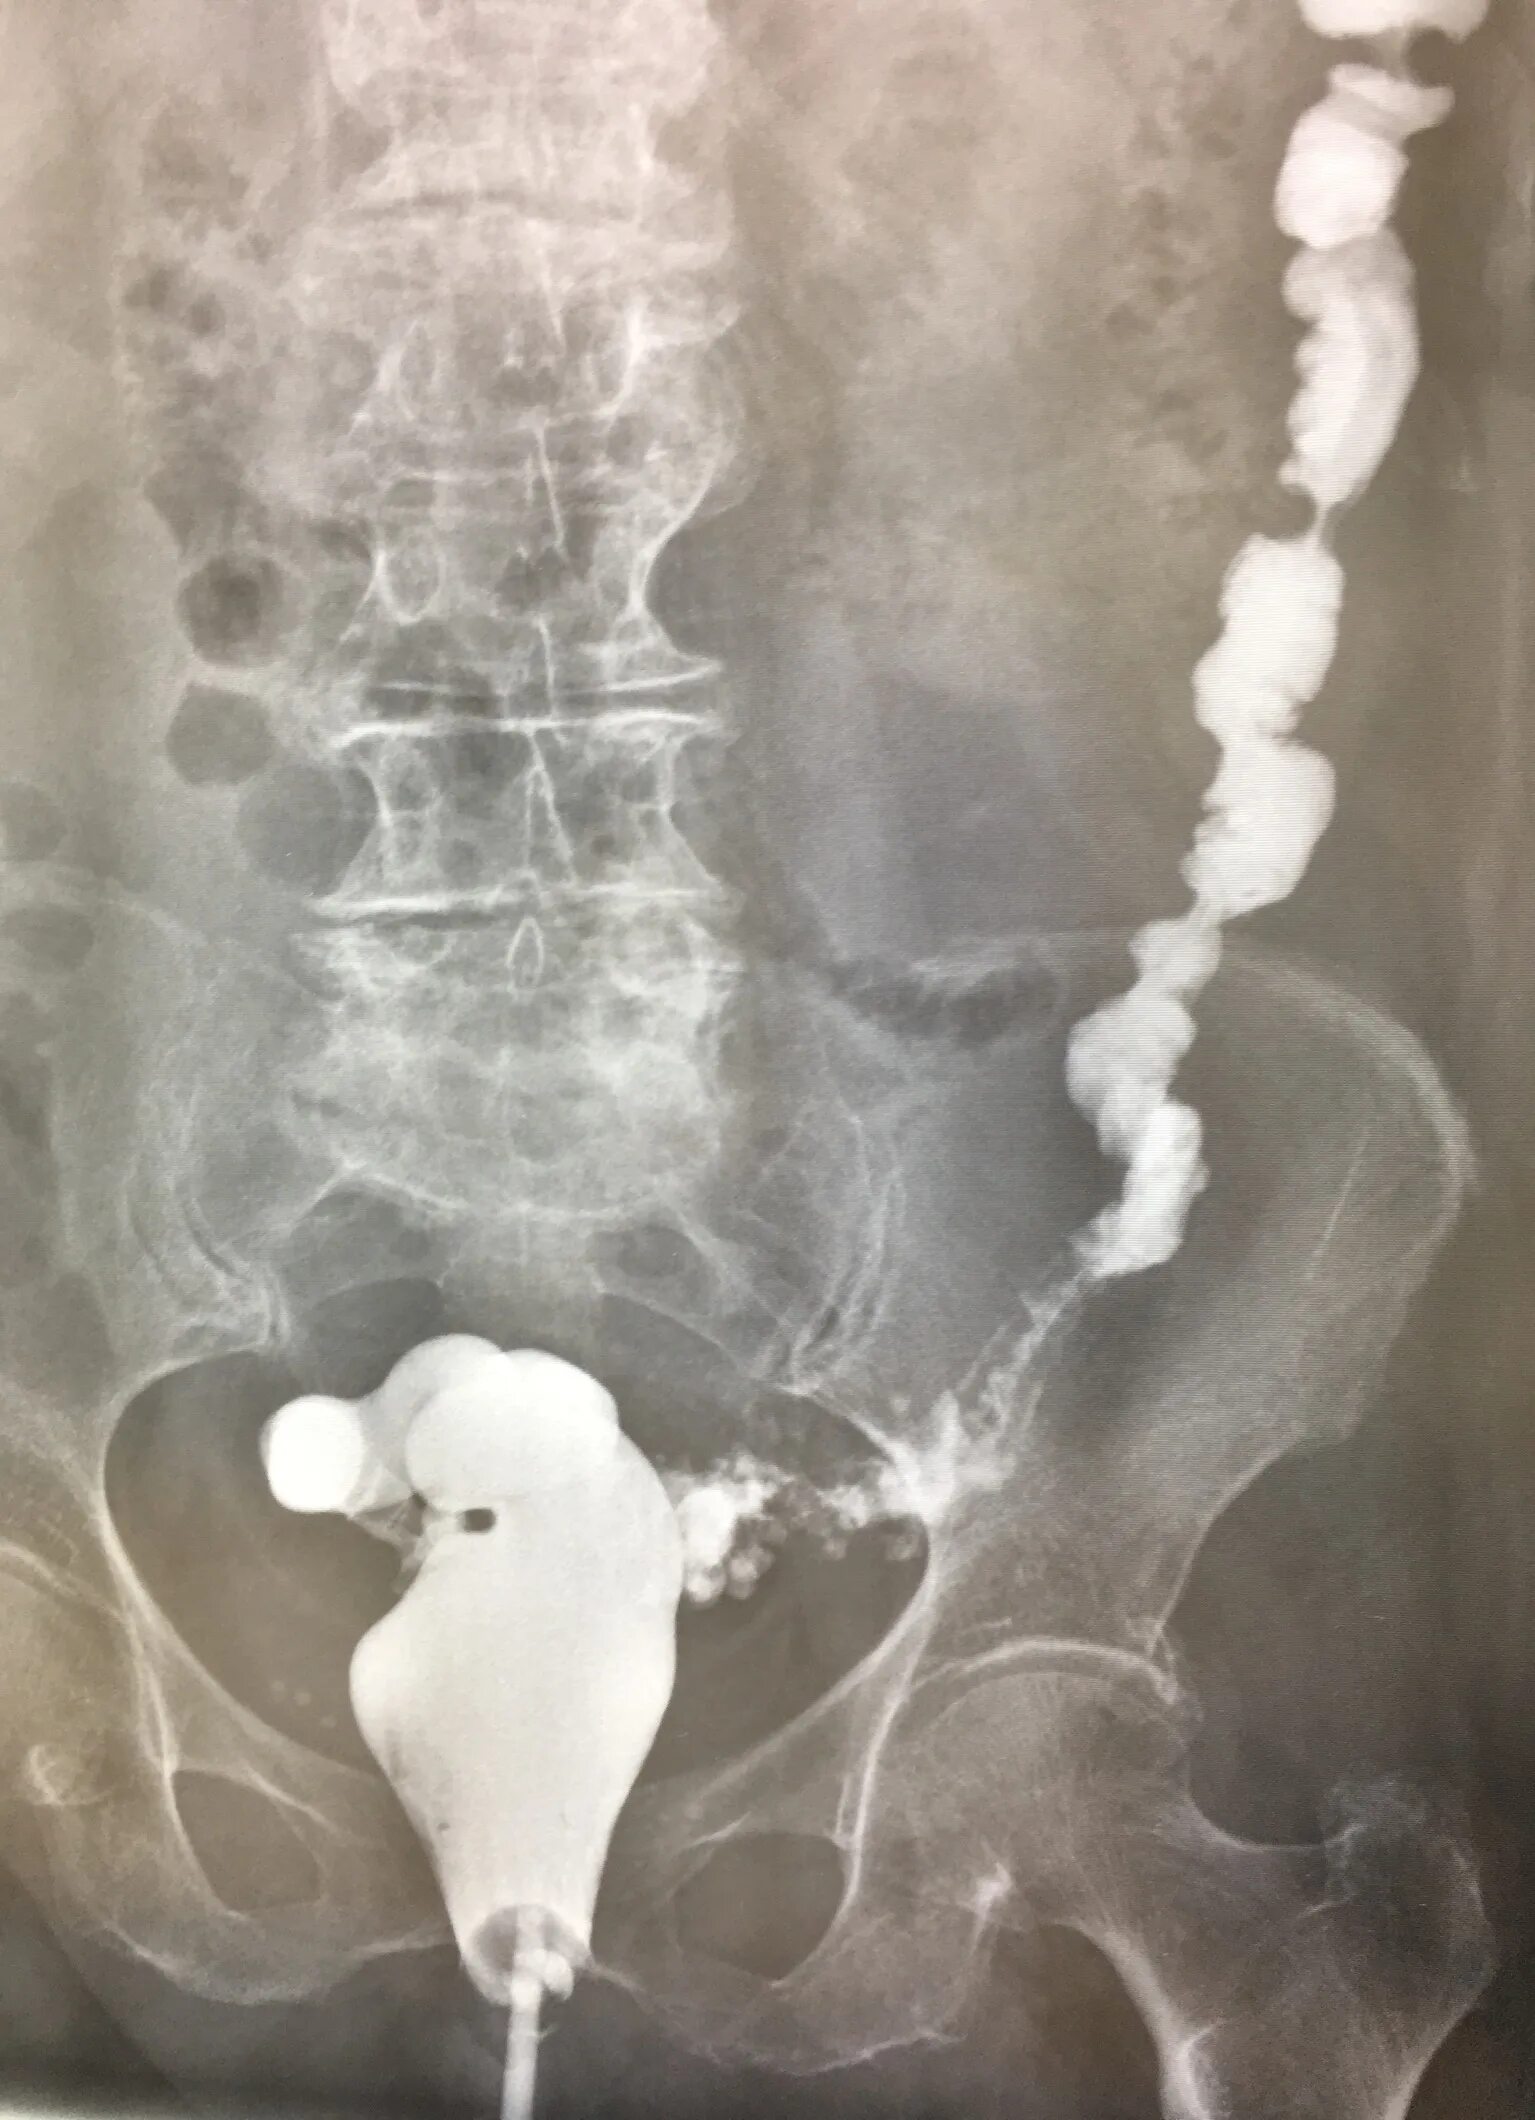

Долихоколон симптомы у взрослых